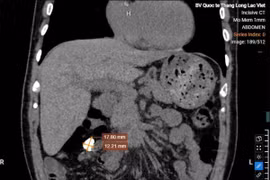

Sau khi thăm khám và chụp XQ, CT Scan, MRI cột sống, cá bác sĩ chẩn đoán bệnh nhân này bị: Vẹo cột sống ngực-thắt lưng bẩm sinh, dẫn tới chèn ép tủy vùng lưng. Sau khi hội chẩn toàn viện, các bác sĩ bố trí cho bệnh nhân tập vật lý trị liệu (tập thở) để chuẩn bị cho cuộc phẫu thuật.

TS.BS Trần Vĩnh Hưng – giám đốc Bệnh viện Đa khoa Khu vực Thủ Đức TP.HCM (trái) đang khám cho bệnh nhân Phạm Thị Th. Đến ngày 13/11, sau hơn 7 giờ phẫu thuật, các bác sĩ đã tiến hành cắt bản sống ngực D11 đến L4 giải ép tủy rễ, bắt 22 vít chân cung từ ngực D6 đến lưng L5 và nẹp 2 thanh nẹp tròn dài 40cm để nắn chỉnh vẹo cột sống ngực thắt lưng và thép xương vùng thắt lưng. Hiện bệnh nhân đã tỉnh táo, có cảm giác và cử động 2 chân tốt. Bệnh nhân đang tập vật lý trị liệu và sẽ ra viện trong vài ngày tới.